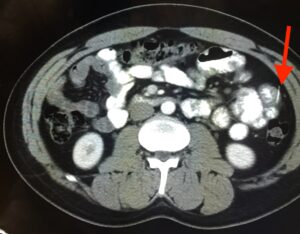

Iatrogenic Bowel Perforation Following Dental Procedure. CT. Annotated. JETem 2025